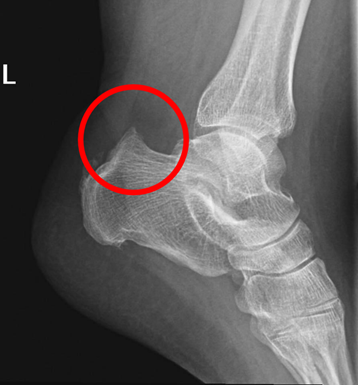

而在2018年芝加哥马拉松赛获得第五名之后,鲁普接受了手术,原因是他被一种名为Haglund畸形的跟骨疾病长期困扰。

Haglund畸形往往发生于先天遗传,这样的人群如果正常生活也许并不发生症状,但如果是运动员,需要反复牵拉跟腱,就容易导致畸形突出处与跟腱发生摩擦,严重时,甚至可以导致跟腱断裂。

而跟腱事实上也是中长跑运动员最容易出现问题的部位之一。